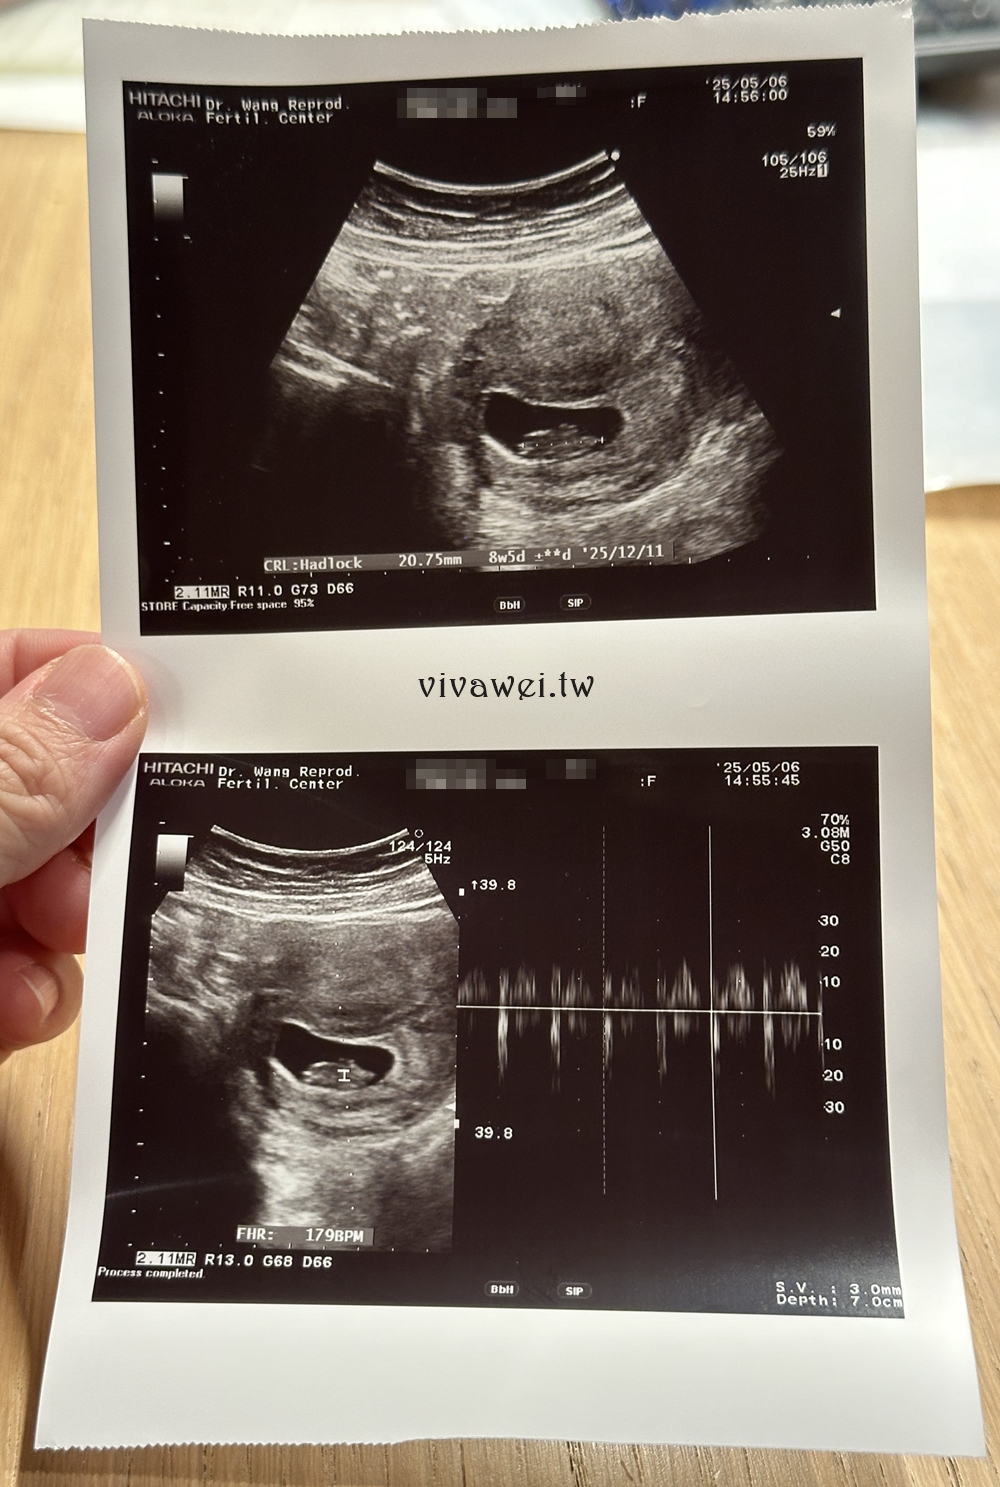

▲今年的結婚周年紀念日去宜蘭慶祝,結束後就想說可以順便經過台北產檢再回家,馬上和診所約了時間去照超音波!這樣我就能少搭一次的火車,可以輕鬆很多!